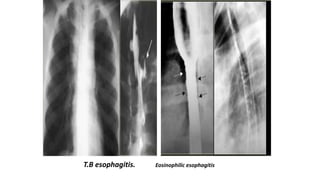

T.B esophagitis. Eosinophilic esophagitis

Cytomegalovirus esophagitis

• Cytomegalovirus esophagitis in a patient with AIDS

• Double contrast esophagram shows a large flat ulcer in profile (large arrows) in the midesophagus

with a cluster of small satellite ulcers (small arrows)

Eosinophilic esophagitis

• small calibre oesophagus.

• • transient or fixed circular rings are

seen.

Cytomegalovirus esophagitis • Cytomegalovirusesophagitis in a patient with AIDS • Double contrast esophagram shows a large flat ulcer in profile (large arrows) in the midesophagus with a cluster of small satellite ulcers (small arrows) •

Eosinophilic esophagitis • smallcalibre oesophagus. • • transient or fixed circular rings are seen.